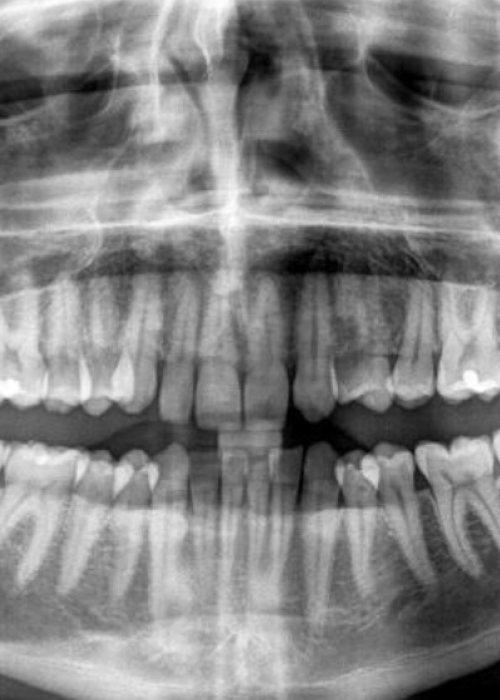

Retención de segundos molares mandibulares: evaluación mediante CBCT y consideraciones terapéuticas ante un caso clínico